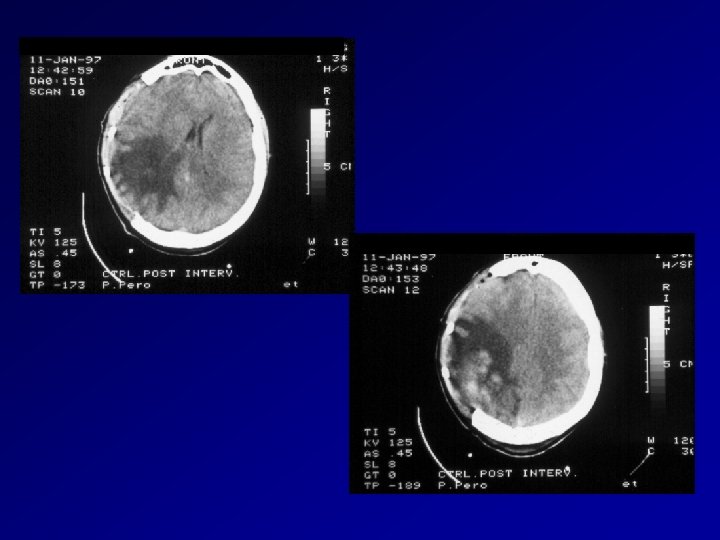

Quadri TAC in sequenza pre e postoperatoria di ematoma subdurale acuto